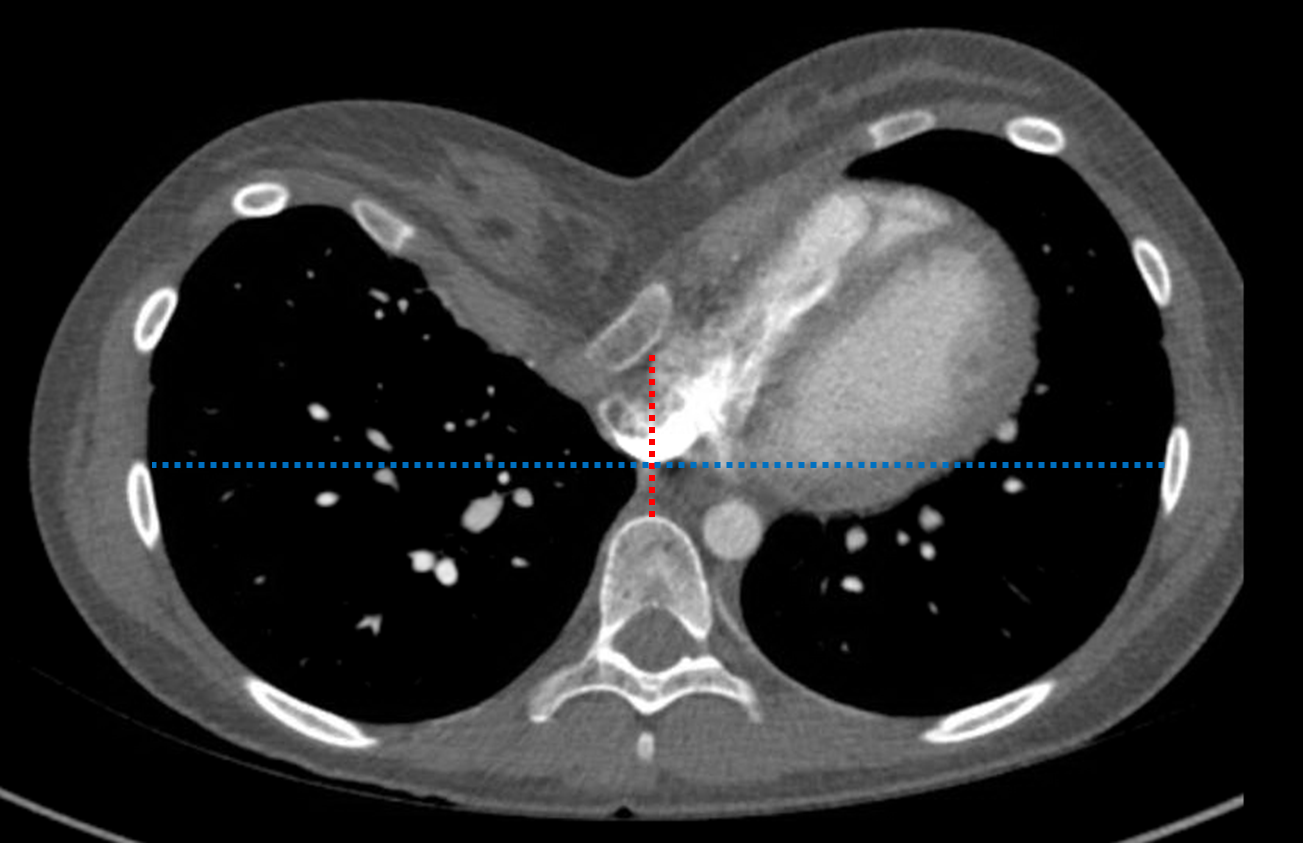

Age: 18

Sex: Female

Indication: Fever, dehydration

Sample ReportHazy opacity along the right heart border on the PA projection is favored to represent a combination of distortion of the right heart by pectus excavatum and atelectasis. No evidence of pneumonia.